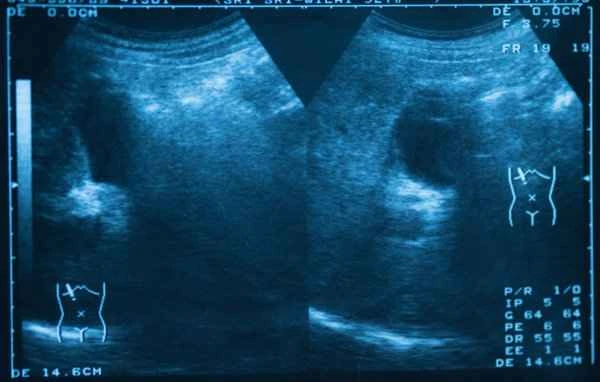

An abnormality on a scrotal color Doppler ultrasound (CDFI) may indicate vascular disease or other related problems within the scrotum. Whether surgical treatment is necessary depends on the specific diagnostic results.

When a color Doppler ultrasound (CDFI) of the scrotum reveals abnormalities, the doctor will conduct a detailed diagnosis based on the specific problem, including but not limited to varicocele, testicular torsion, and testicular tumors. The treatment methods for these conditions differ, but the need for surgical intervention usually depends on the severity and specific type of the condition. For example, in the case of varicocele, if the symptoms are significant or it affects fertility, varicocelectomy may be necessary; while in the case of testicular torsion, this is an emergency requiring immediate surgery to restore blood flow to the testicle and prevent testicular necrosis.